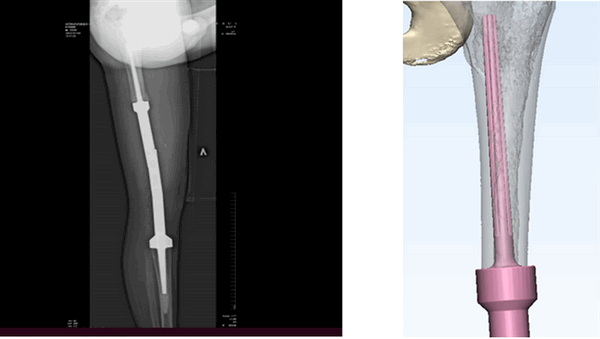

Эндопротезирование

Эндопротезирование является вариантом органосохраняющего вмешательства. Это операция по замене сустава имплантами, которые имеют анатомическую форму здорового сустава и позволяют выполнять весь объем движений. Чаще используется тотальное эндопротезирование из-за невозможности сохранения сустава (рис. 5).

Рис. 5. Тотальное эндопротезирование коленного сустава состоит из трех компонентов: бедренного, большеберцового и надколенникового